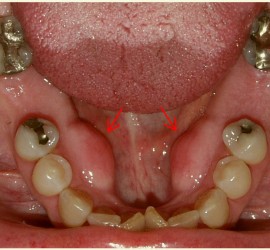

Этиология и патогенез. Возникает при осложнениях периодонтитов моляров, остеомиелита угла и ветви челюсти, из-за заноса инфекции при инъекции анестетиков. Клиническая картина. Появляется боль при открывании рта, затем при глотании. Асимметрия лица незначительная, так как инфильтрат располагается за ветвью нижней челюсти. Повышение температуры тела до 38—39° С, контрактура жевательных мышц, увеличение […]